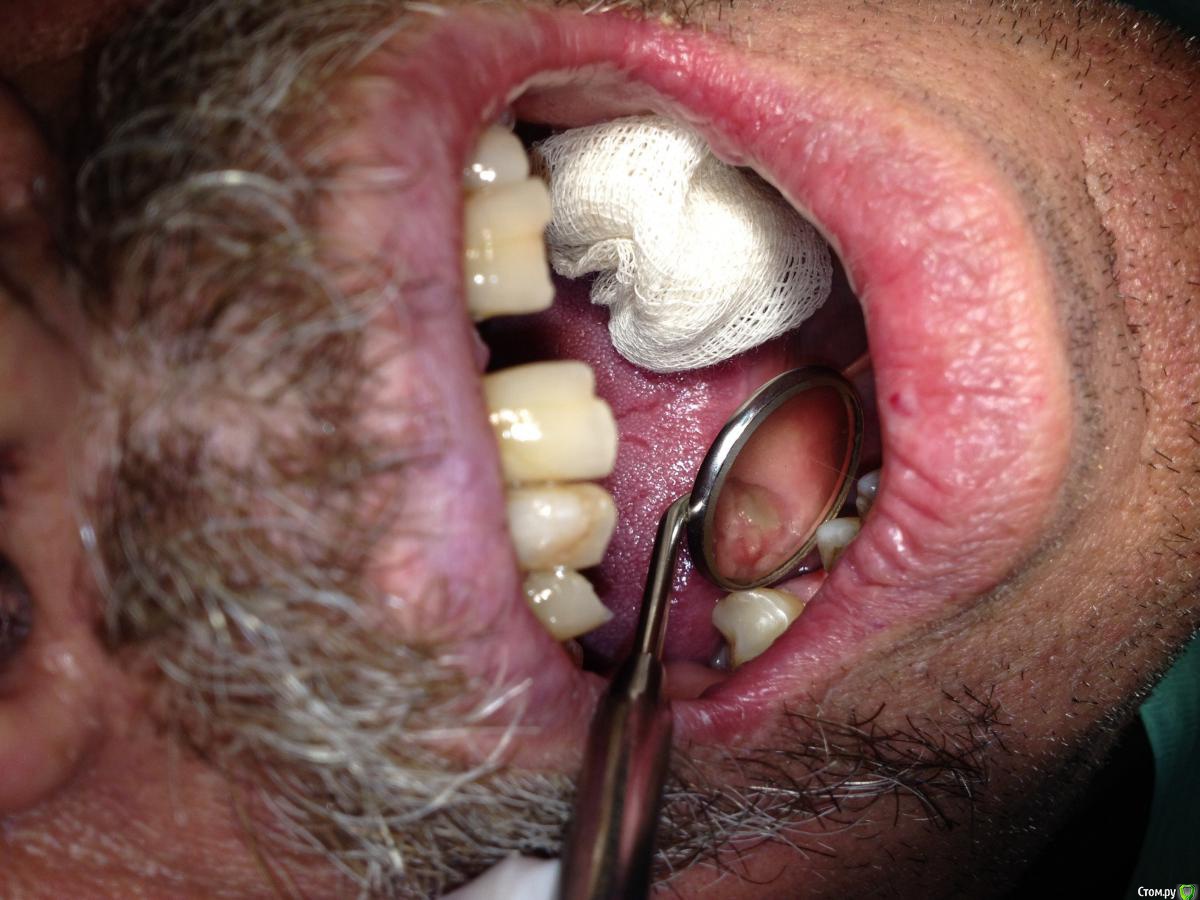

Shakirbura Опубликовано 11 октября, 2015 Поделиться Опубликовано 11 октября, 2015 Уважаемые коллеги! Помогите начинающему имплантологу, плиз.Был установлен одиночный имплантат adin 5,0х10 mmВид через 10 дней. Пациента беспокоит только небольшая парестезия в области подбородка (во время операции сверло чуть провалилось в канал). Что произошло с лоскутом? Это некроз? Почему так получилось?За фото извините, что под рукой было на то и снял. Ссылка на комментарий

Aquarius Опубликовано 11 октября, 2015 Поделиться Опубликовано 11 октября, 2015 Ну швы разошлись, а то что немного провалились это нехорошо Ссылка на комментарий

колесников Опубликовано 11 октября, 2015 Поделиться Опубликовано 11 октября, 2015 Либо сильно задавили швами,либо инфильтрация местно анестетиком с вазоконстриктором 1:100000. Ишемия = некроз. Торк какой был? Ссылка на комментарий

Shakirbura Опубликовано 11 октября, 2015 Автор Поделиться Опубликовано 11 октября, 2015 Торк не мерил, но имплант заходил довольно плотно. Последним сверлом не проходил. Швы плотно завязал, да. анестетик 1:100000 Ссылка на комментарий

колесников Опубликовано 11 октября, 2015 Поделиться Опубликовано 11 октября, 2015 Торк не мерил, но имплант заходил довольно плотно. Последним сверлом не проходил. Швы плотно завязал, да. анестетик 1:100000Адин довольно агрессивный. На 1/2, хотябы, надо последним сверлом проходить на н.ч. 1:100000 прикреплённую слизистую не инфильтрировать. Перед ушиванием обязательно мобилизовать,чтобы лоскут перекрывал легко без натяжения. Ушивать п-образным швом + 2-3 узловых без излишнего давления,иначе слизистая отечёт и швы прорвутся. 1 Ссылка на комментарий